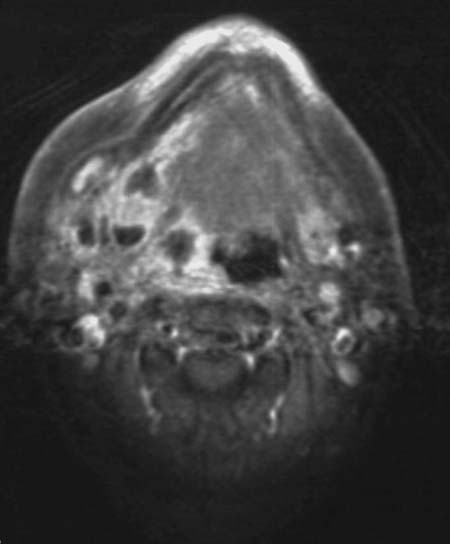

In der T1-gewichteten Sequenz mit Kontrastmittel im Bereich der Mundhöhle kommt die rechte Tonsillenregion deutlich vergrößert mit Signalsteigerung zur Darstellung. Innerhalb der Raumforderung befinden sich signalarme Bereiche im Sinne von Nekrosen.

Die Raumforderung reicht bis in die Halsweichteile und in den Mundboden.

Peritonsillarabszess